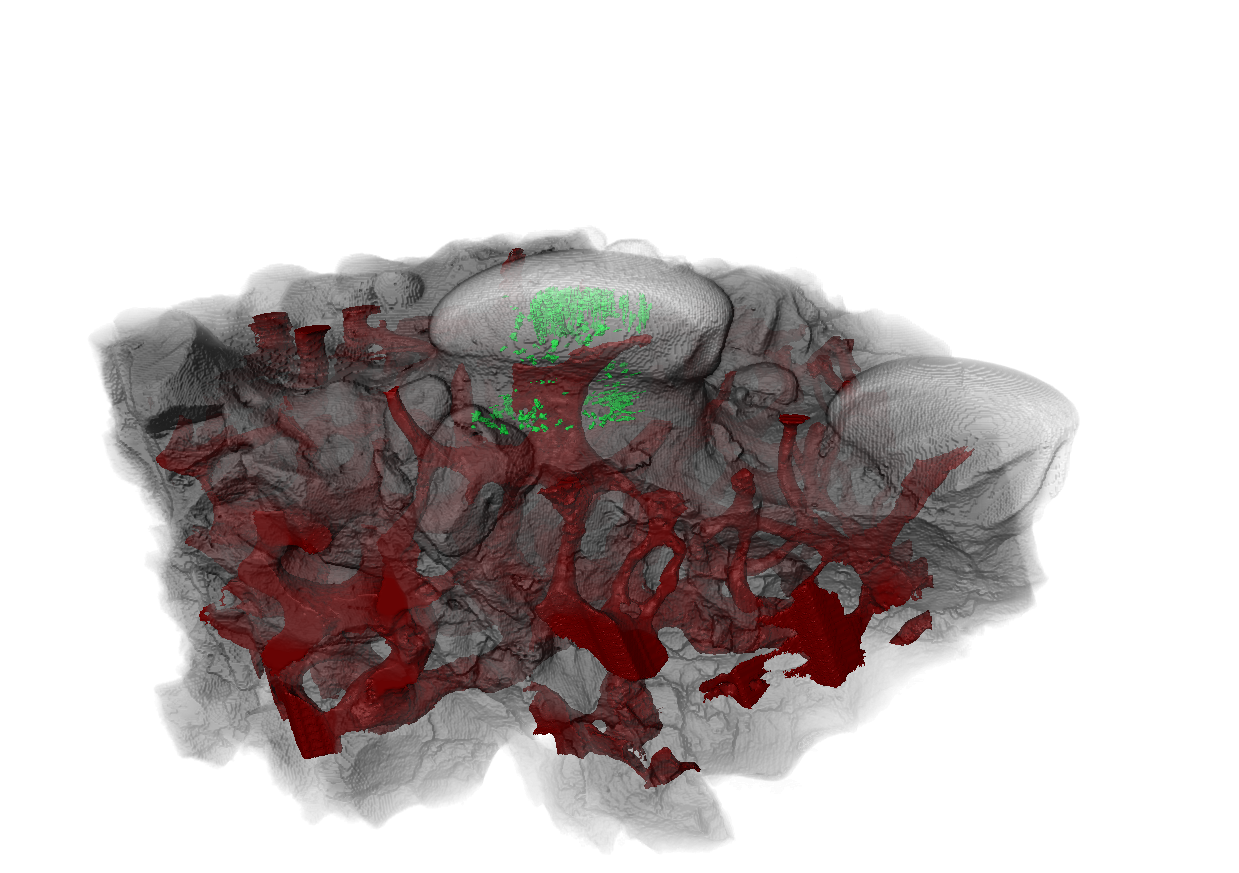

古代无颌脊椎动物鱼“Astrapsis”的齿状结构CT扫描图。图中绿色小管内填充着牙本质,这种物质也构成了现代牙齿敏感的内层。红色部分是血管系统,在生命早期,血管系统可能容纳神经,从而传递感觉。图片来源:芝加哥大学

美国芝加哥大学科学家最近发现,人类牙齿内部的牙本质,也就是对冷热酸甜敏感的那层结构,最早是由远古鱼类带甲外骨骼中的感觉组织演化而来的。

大约在4.65亿年前的奥陶纪,早期脊椎鱼类全身覆盖着坚硬的铠甲。这些甲胄上布满微小的凸起结构,内部含有类似牙本质的组织。科学家推测,这些结构能感知周围水流的压力、温度的变化,甚至能探测到靠近的掠食者,就像一套“水下雷达系统”。